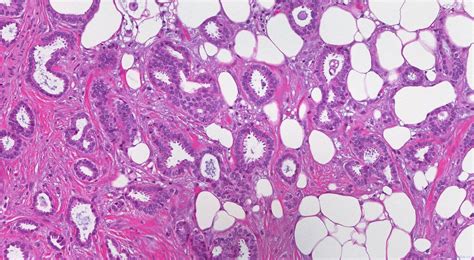

The diagnosis of invasive carcinoma typically involves a combination of physical exams, imaging studies (like mammograms, ultrasounds, and MRIs), and a biopsy. Once invasive carcinoma is confirmed, doctors will determine the stage and grade of the cancer. Staging refers to the extent of the cancer’s spread, while grading describes how abnormal the cancer cells look under a microscope. These factors play a crucial role in determining the best course of treatment, which may include surgery, radiation therapy, chemotherapy, hormone therapy, and targeted therapies.